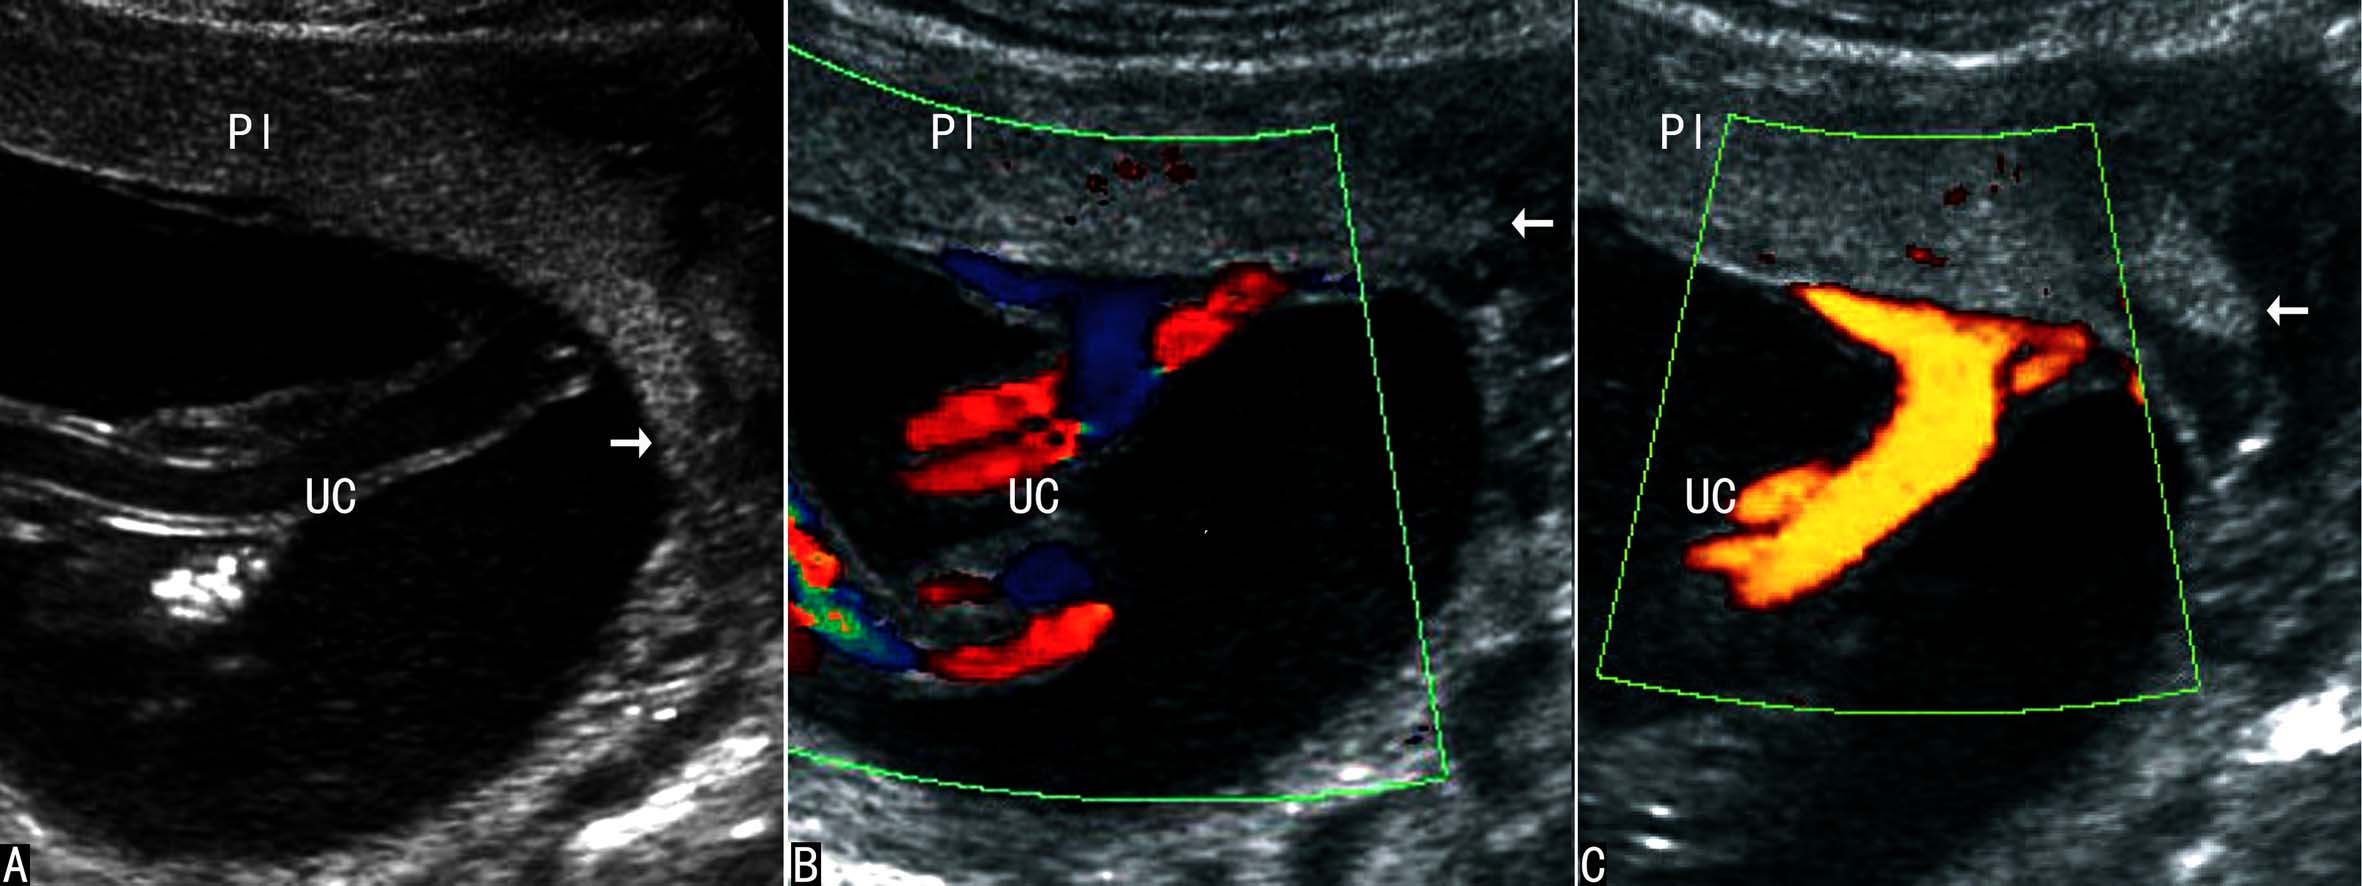

脐带边缘附着时超声显像检查可以发现脐带附着于胎盘边缘,一般以距边缘≤2cm为诊断标准;脐带进入胎盘前脐带血管维持正常的绞合状态,脐带结构和血流多不受影响(图2)。当脐带血管进入胎盘以前已经失去正常的绞合状态则形成脐带帆状附着,脐带血管分离后其周围无胎盘组织显示。彩色多普勒血流显像及三维超声显像检查可以显示脐带附着处的血流及其空间结构,更有利于显示脐带血管与胎盘的关系,有利于显示脐带帆状附着(图3)。

在晚期妊娠过程中,由于羊水量相对减少,胎体在羊膜腔内占据的空间比较大,常常影响脐带根部的显示和胎盘的完整显示;在中期妊娠过程中,羊水量相对较多,尤其是能够通过孕妇体位的改变将胎体和胎盘子体面分开,在羊水无回声区内多可清晰地显示胎盘回声,显示脐带根部与胎盘的关系即可明确脐带的附着部位,观察脐带根部的血管回声状况可以辨别脐带边缘附着(图2)和脐带帆状附着(图3)。彩色多普勒血流显像可以明确地显示脐带血管及血管与胎盘的关系,多普勒能量图显示不受血流方向和速度的影响,对脐带血管和胎盘血管的显示更有利,对边缘附着和帆状附着的诊断会更有意义。

图2脐带边缘附着

图3脐带帆状附着